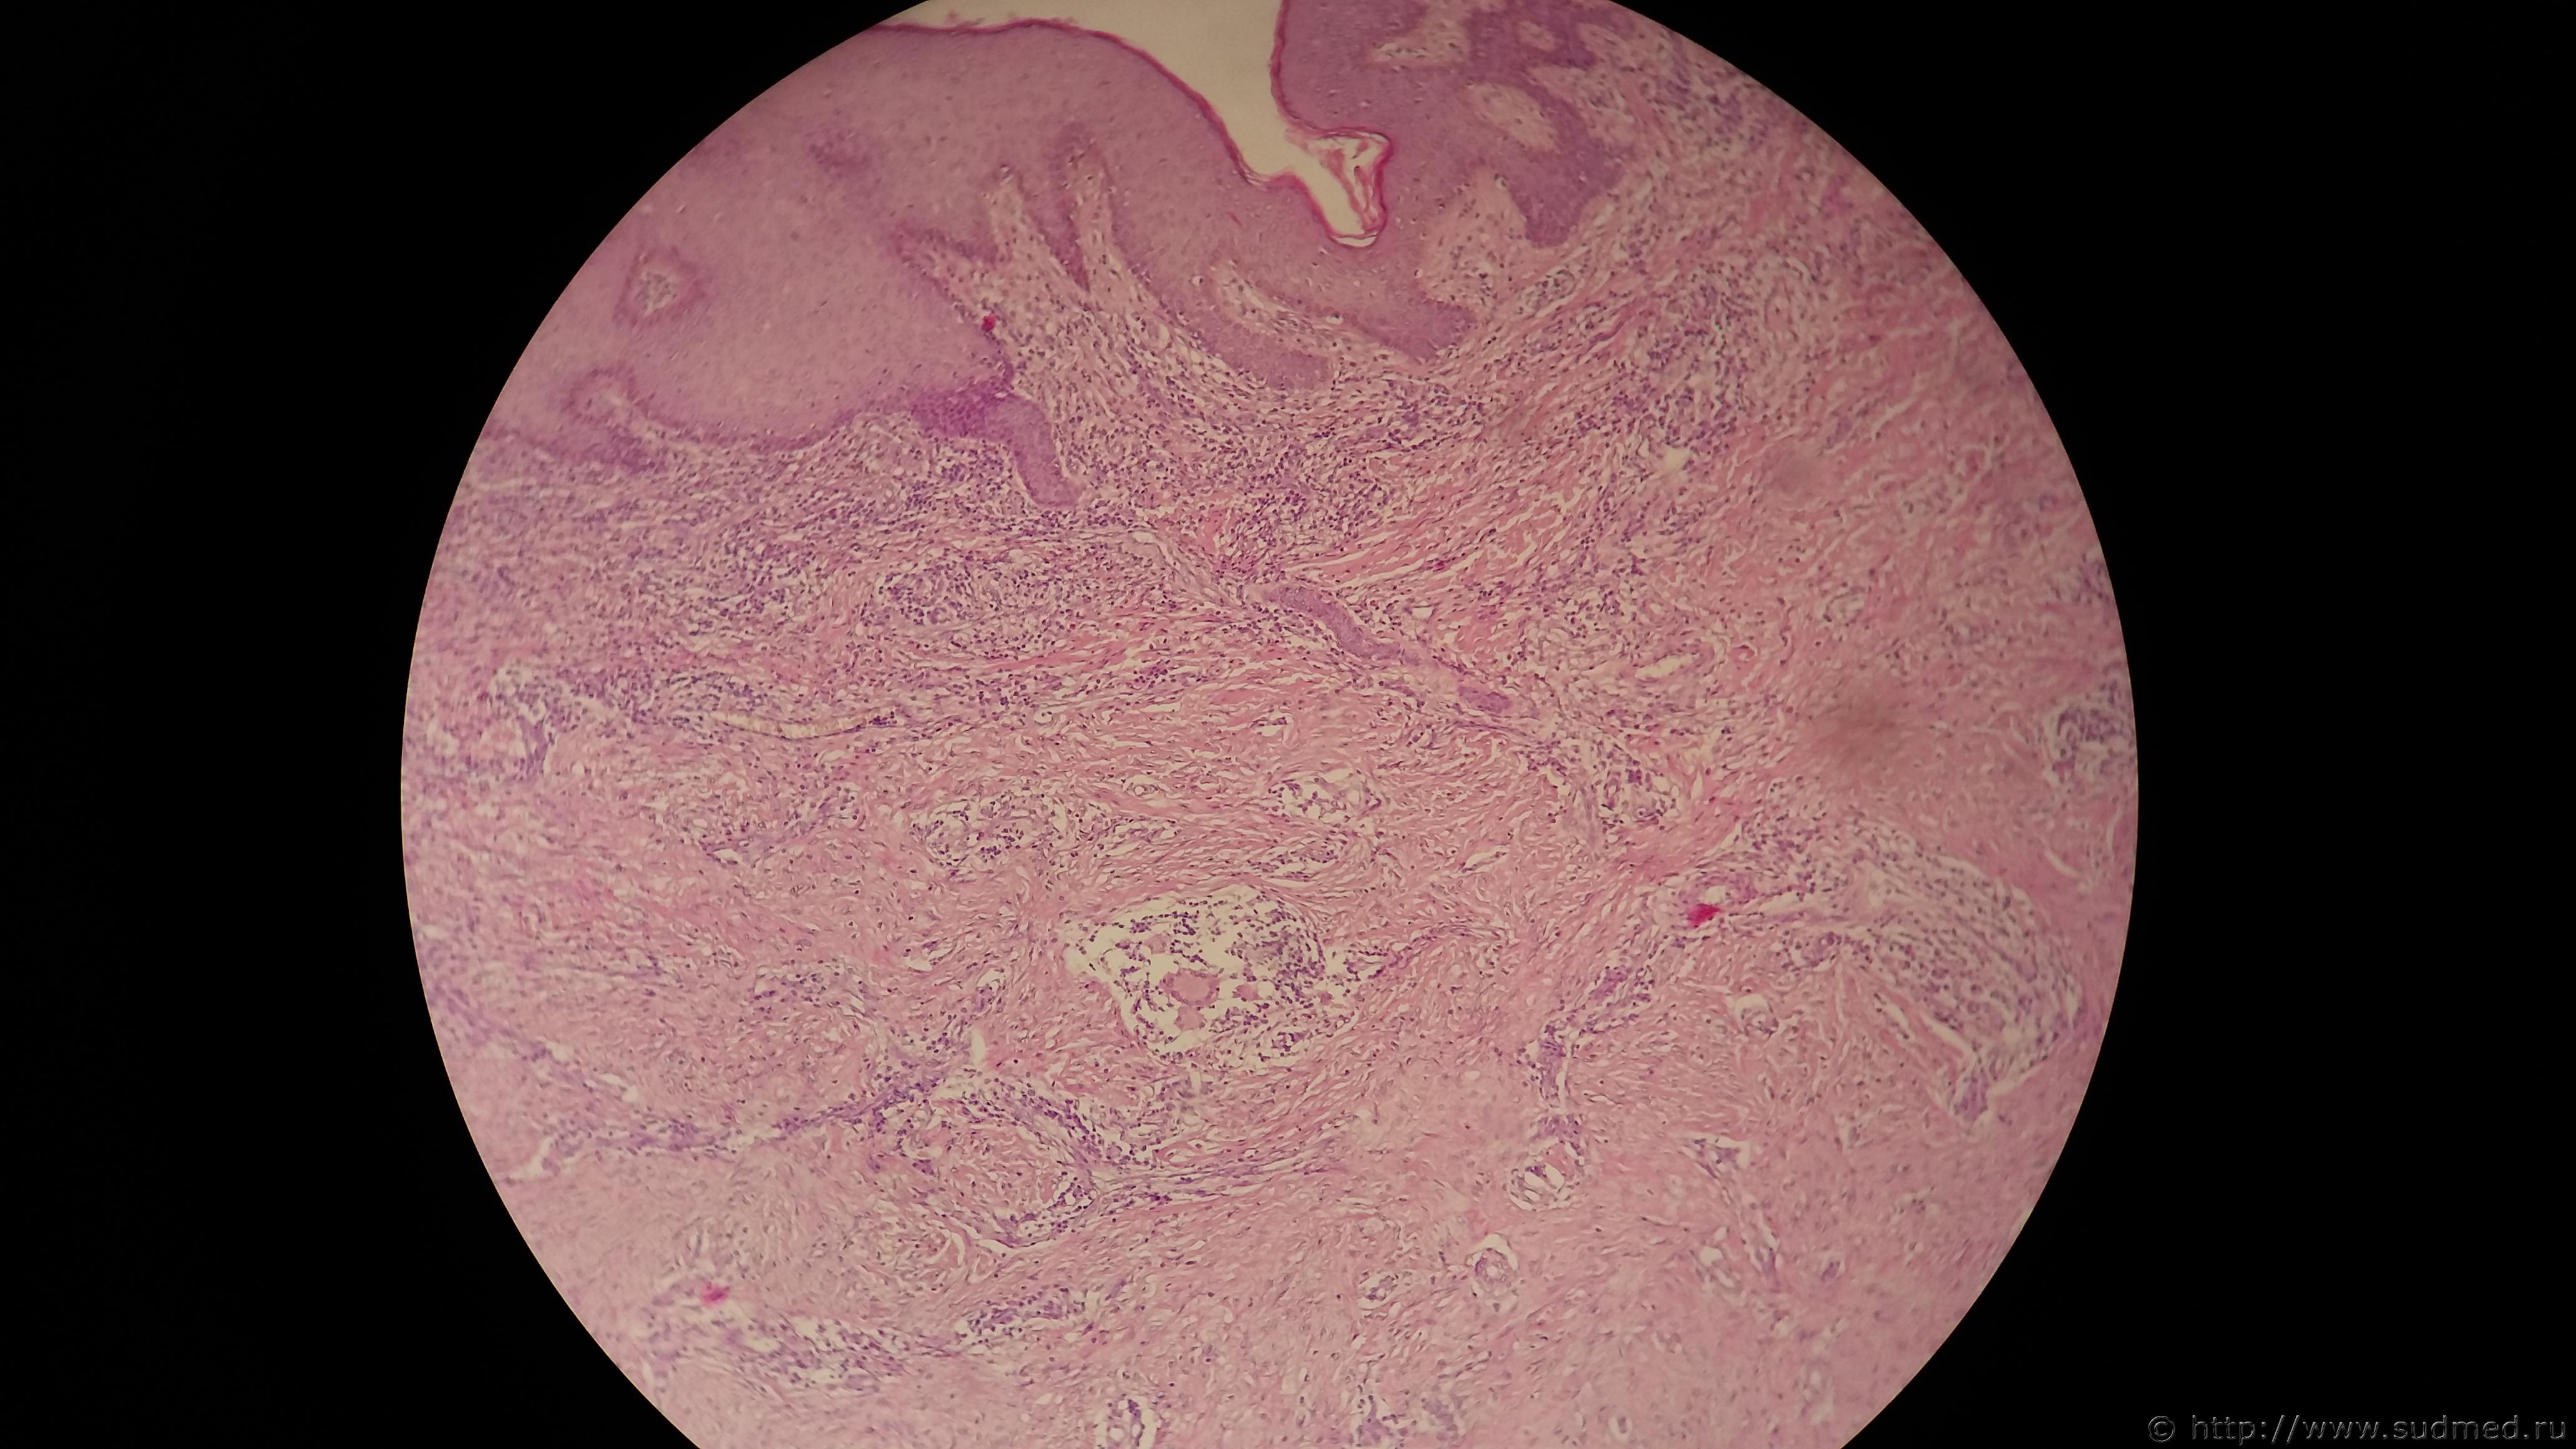

Мужчина 30 лет. Страдает костным туберкулезом, Судебная медицина - Прикрепленное изображениеосложненным секвестрацией со свищевым каналом вплоть до повреждения кожи. Диагноз: Туберкулезный остеомиелит, который четко виден на микрофото и по ходу свищевого канала видны очаги казеозного некроза с эпителиоидными клетками, лимфоцитами и многоядерными клетками Пирогово-Ланхганса.